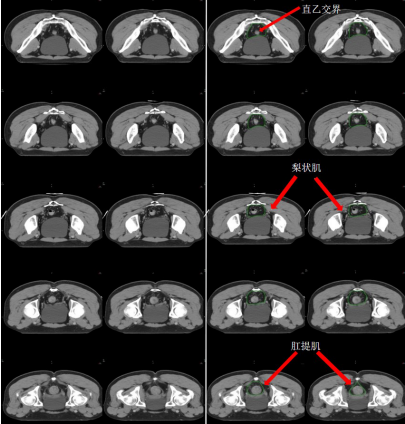

b) 直肠系膜区-M(深绿) (图 7),边界:

上界:肠系膜下动脉分叉为乙状结肠动脉与直肠上动脉处/直乙交界;

下界:肛提肌插入外括约肌处/直肠周围系膜脂肪组织消失处;

前界上:直肠上动脉前缘扩 0.7 cm;

前界中/下:直肠系膜筋膜,前方盆腔器官的后界;

后界:盆腔骶前区的前界;

外界上:侧方、髂外淋巴结区的内侧;

外界中:直肠系膜筋膜,侧方淋巴结区的内侧;

外界下:肛提肌内侧缘。

图 7 直肠癌直肠系膜区 CTV 勾画示例